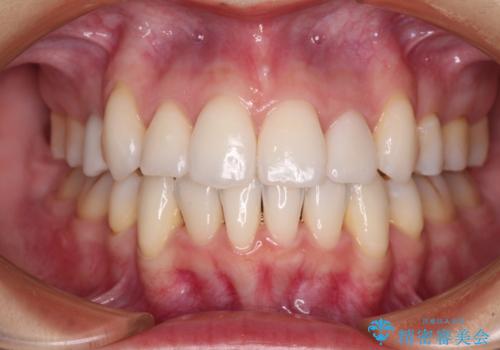

PGAクラウンにしたことで咬み心地に全く違和感がなく、気にされていた審美面も、奥歯でありそれほど目立たないこともありますが、白金加金の色を気に入っていただけたので、患者様には大変満足していただけました。